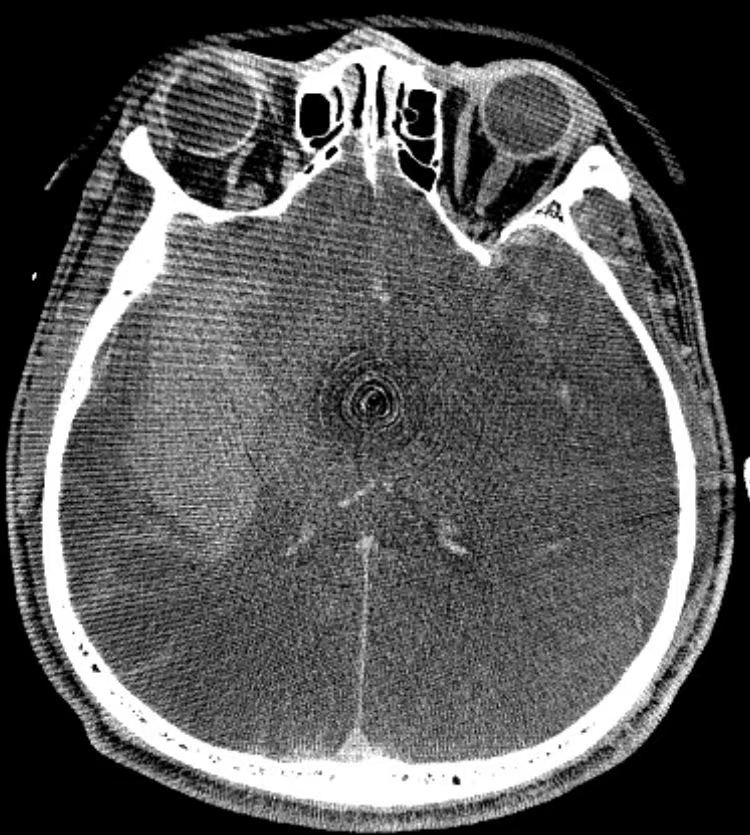

患者男性,40岁,既往体健。主因“头痛2天,加重1天”就诊于清华大学附属垂杨柳医院急诊科。查体:嗜睡,可对答,双侧瞳孔等大。急诊头颅CT显示蛛网膜下腔出血,CTA提示右侧大脑中动脉M1段分叉动脉瘤。

CT提示蛛网膜下腔出血